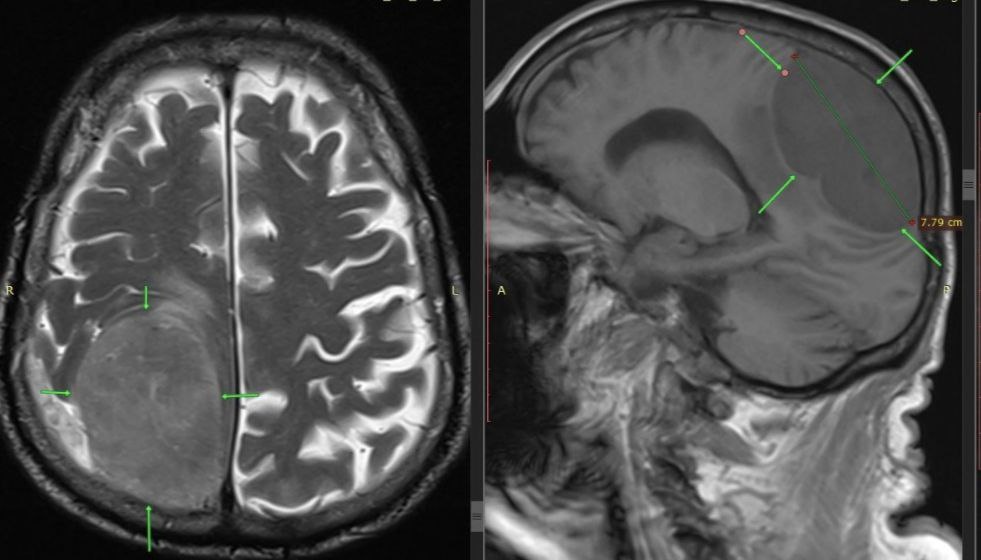

Когда 85-летний мужчина поступил в больницу у него уже отказала левая нога и левая половина тела. Изначально врачи подозревали инсульт. Но после проведеденного экстренного обследования, выяснилось, что его жизни угрожает опухоль размером 8x7 см.

Мужчине провели срочную операцию. Нейрохирурги Пятигорска выполнили трепанацию черепа и полностью удалили опухоль.

Пенсионер быстро пошёл на поправку, активность в левой половине тела восстановились. Гистология выявила доброкачественный характер новообразования.